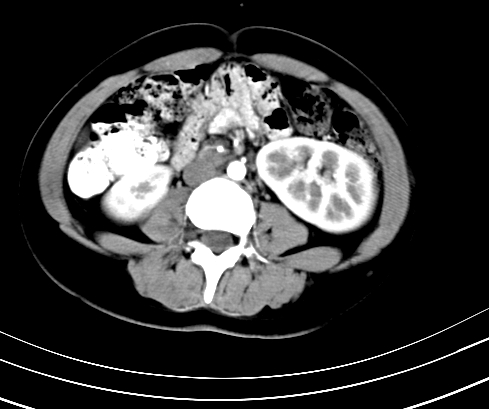

静脉期